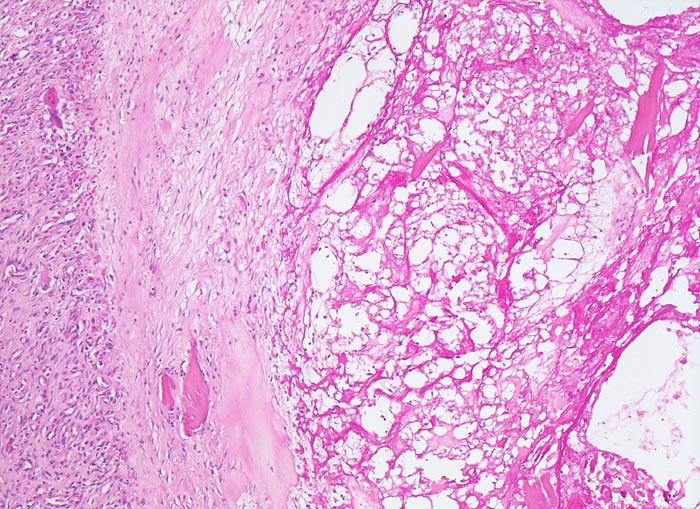

PathoPic – image database / PathoPic ID 4771 - Coxarthrose: Geröllzyste

Coxarthrose: Geröllzyste

Trauma / mechanischer Schaden

Knochen, Femurkopf

Knochen, Knorpel, Gelenke

74-jährige leicht adipöse Patientin mit Anlaufschmerz, belastungsabhängigem Schmerz und zunehmender Versteifung im Hüftgelenk. Im Röntgenbild des Hüftgelenks zeigen sich eine Gelenkspaltverschmälerung, subchondrale Osteolysen, Usuren und randständige Osteophyten.

Histologie

50